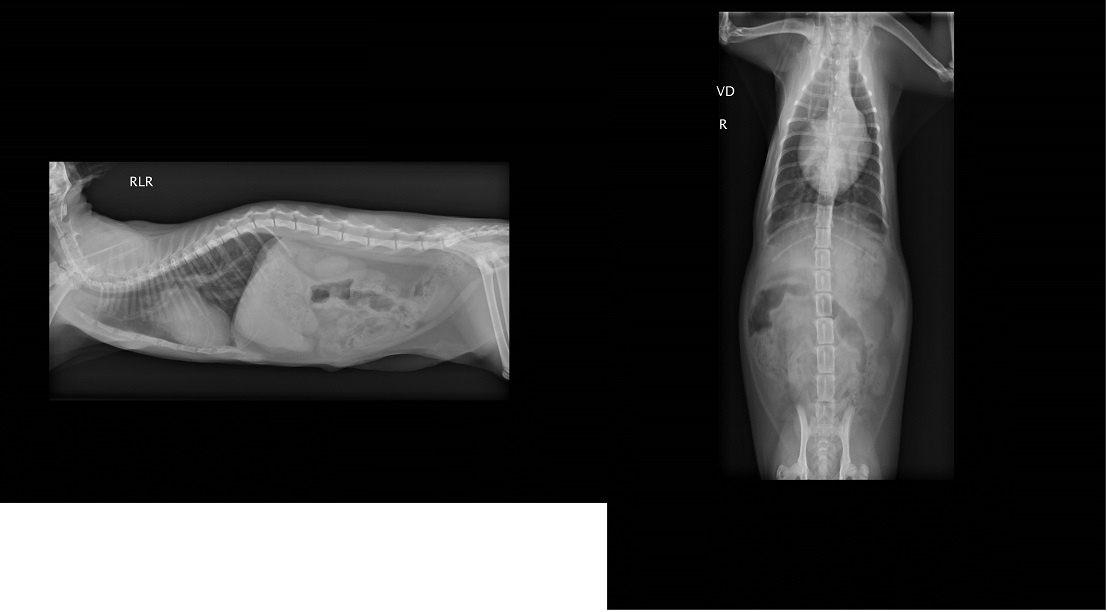

x光檢查發現腹腔赫尼亞,胎兒隨著破洞掉到後腳,當天血檢白血球過高,恐怕已經有感染的狀況,

貂蟬尤其嚴重,呼吸得很用力非常倦怠,緊急送往醫院檢查,醫師懷疑可能有心臟方面的疾病,建議轉診道心臟專科"專心動物醫院"進行心臟超音波檢查,

檢查結果心跳超快已有肺氣腫情況,診斷為PDA(開放性動脈導管),開放性動脈導管是一種常見天生的心臟狀況

,在母體中血流的需求與出生後不同,而在主動脈與肺動脈之間有一條相通的血管,稱為動脈導管,

通常這條血管會在出生後兩三天之內關閉,而貂蟬出生之後動脈導管沒有關閉,

導致血流會從大動脈轉而流向肺動脈,一般會有易倦、生長停滯、咳嗽、呼吸速率增加、喘息等等狀況,

而此次鼻氣管炎使得狀況更加明顯危急,貂蟬住了一週氧氣室才撿回一命,這種先天性心臟病可透過手術治療,

但需至少體重要到達2公斤才可手術,在這期間,貂蟬需每日服用心臟藥物以控制肺高壓形成。動物近況說明: 貂蟬的體重達到2公斤後,9/25約診專心洪醫師做術前評估,心臟超音波顯示肺高壓嚴重,開刀迫在眉睫,

故經由志工的幫忙順利約診亞太葉力森醫師為貂蟬進行封閉永存性動脈導管的手術,

10/13日進行手術,手術順利成功,歷經了開胸手術的貂蟬,10/5即離氧至一般籠,讓人欽佩貂蟬旺盛的生命鬥志,

目前狀況順利恢復中,10/12至專心回診,PDA造成的心雜音已幾乎消失,但仍有因為鬰血性心衰竭引起的二間瓣閉鎖不全,

預定11/13再回診專心,以確定PDA的封閉狀況,10/17已拆線,接回協會照顧。